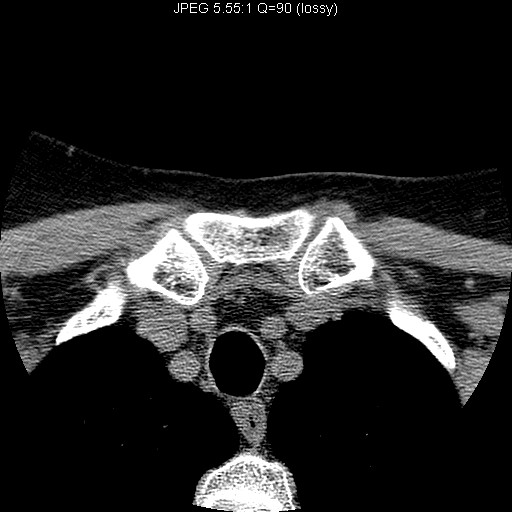

Identify the sternoclavicular joint. Click the image for labeling.